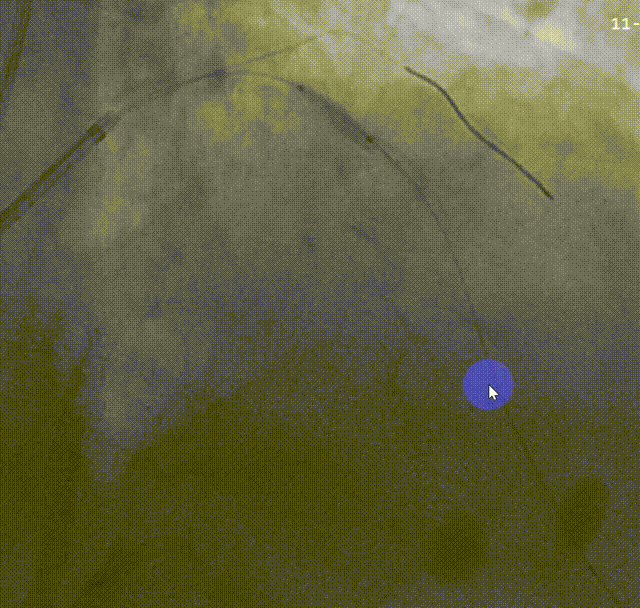

蜘蛛位造影提示LM、LAD重度狭窄伴钙化